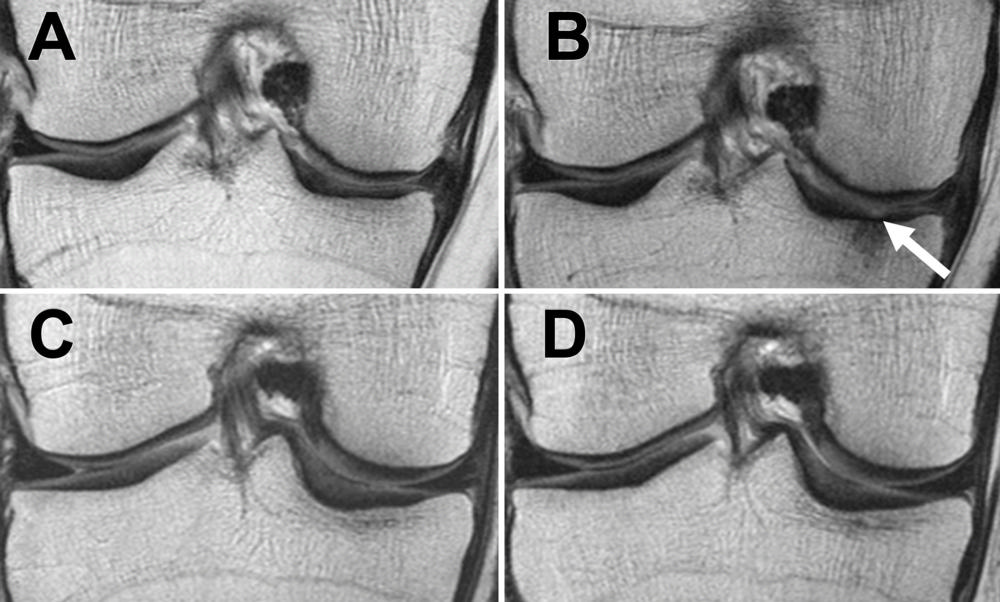

Researchers at the University of California, San Francisco, looked at the degeneration of menisci, articular cartilage and bone marrow in the knee joint, according to the study’s lead author, Alexandra Gersing, MD, Department of Radiology and Biomedical Imaging.

In addition to slowed articular cartilage degeneration, researchers also saw changes in the menisci after weight loss.

“The most exciting finding of our research was that not only did we see slower degeneration in the articular cartilage, we saw that the menisci degenerated a lot slower in overweight and obese individuals who lost more than five percent of their body weight, and that the effects were strongest in overweight individuals and in individuals with substantial weight loss,” Dr. Gersing said.